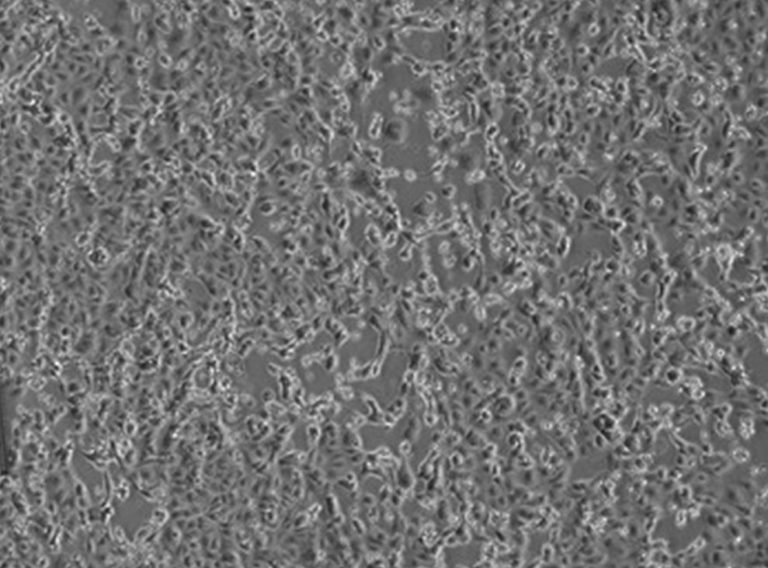

Coronavirus, in terapia intensiva un 38enne in Lombardia

MILANO (ITALPRESS) – “Un 38enne italiano e’ risultato positivo al test del coronavirus. Sono in corso le controanalisi a cura dell’Istituto Superiore di Sanita’. L’uomo e’ ricoverato in terapia intensiva all’ospedale di Codogno (Lodi) i cui accessi al Pronto soccorso e le cui attivita’ programmate, a livello cautelativo, sono attualmente interrotte. Le persone che sono state a contatto con il paziente sono in fase di individuazione e sottoposte a controlli specifici e alle misure necessarie”. Lo comunica in una nota l’assessore al Welfare della Regione Lombardia Giulio Gallera.

Maggiori dettagli saranno illustrati nel corso di una conferenza stampa che si svolgera’ nella mattinata di oggi.